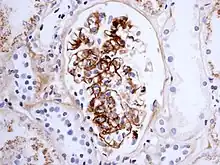

As observed under methods of histopathology, acute necrotizing vasculitis within the affected tissues is observed concomitant to neutrophilic infiltration, along with notable eosinophilic deposition (fibrinoid necrosis). Often, immunofluorescence microscopy can be used to visualize the immune complexes.[10] Skin response to hypersensitivity of this type is referred to as an Arthus reaction and is characterized by local erythema and some induration. Platelet aggregation, especially in microvasculature, can cause localized clot formation, leading to blotchy hemorrhages. This typifies the response to injection of foreign antigen sufficient to lead to the condition of serum sickness.[11]